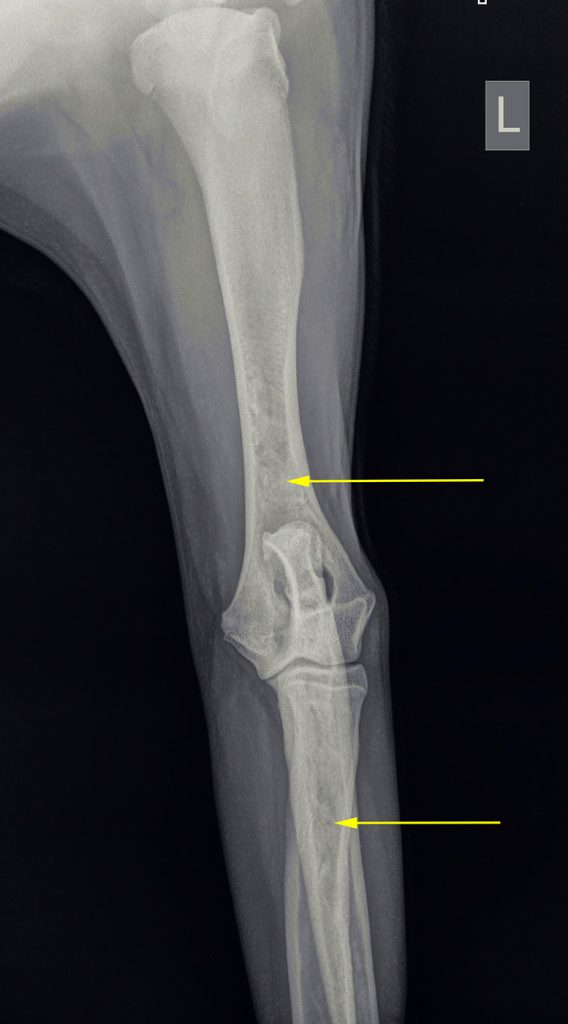

Op röntgenfoto’s kan groeipijn vaak zichtbaar gemaakt worden; het uit zich als wolkvorming in de mergholtes van de lange botten. De pijnlijkheid kan meestal met pijnstilling opgelost worden. Omdat het echter alle lange botten kan aantasten, wisselt de kreupelheid die hiermee gepaard gaat regelmatig van poot. Het kan dan ook voorkomen dat de kreupelheid in bijvoorbeeld de voorpoot overgaat, om na een maand in de achterpoot op te treden.